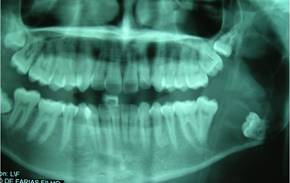

Male patient of African descent aged 17, a student born in Fortaleza, state of Ceará, Brazil, sought care in a private dental clinic with complaints of mouth suppuration. The patient’s mother informed us that he had felt a bad taste in his mouth for about a month. A clinical dental surgeon ordered a panoramic x-ray of the jaws, detected the lesion, and referred him to an oral and maxillofacial surgeon. His medical history did not include any complaints of pain: he had only reported a bad taste in the mouth and bad breath. The extraoral physical examination showed symmetrical facies and absence of facial deformities. Nodal chains of the cervicofacial complex presented no alterations. On intraoral examination, a suppuration was visible in the lingual and distal gingival sulcus in the region of tooth 37. There was a discrete elevation in the region of the left retromolar trigone with fluctuation point and liquid consistency. The panoramic radiograph showed an extensive osteolytic lesion in the left mandibular angle and ascending branch region, of expansive appearance, associated to and including tooth 38, displaced towards the basilar bone (Fig. 1).